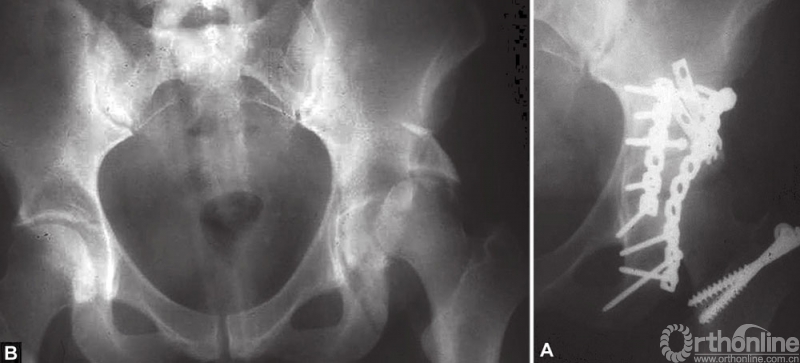

A和B髋臼后壁合并后柱骨折的固定

45岁男性患者,交通事故导致左侧髋臼后柱及后壁骨折。注意骨折线向上延伸以及髋臼顶的骨块。选择后侧入路,以两块钢板固定。同时进行关节囊外大转子截骨并以两枚螺钉固定。